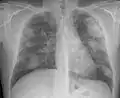

Complicated silicosis

Silicosis ILO Classification 2-2 R-R

- Complicated silicosis

- Silicosis can become "complicated" by the development of severe scarring (progressive massive fibrosis, or also known as conglomerate silicosis), where the small nodules gradually become confluent, reaching a size of 1 cm or greater. PMF is associated with more severe symptoms and respiratory impairment than simple disease. Silicosis can also be complicated by other lung disease, such as tuberculosis, non-tuberculous mycobacterial infection, and fungal infection, certain autoimmune diseases, and lung cancer. Complicated silicosis is more common with accelerated silicosis than with the chronic variety.